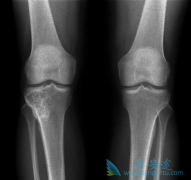

既往骨折史是未来脆性骨折强有力的预测因素之一。在FREEDOM研究中, 地诺单抗 (denosumab)可以显著降低患者新发椎体、非椎体以及髋骨骨折的风险。FREEDOM事后分析,旨在阐明地诺单抗在既往有骨折史的受试者二次脆性骨折预防中的疗效。共计8087名女性被 ...

• 地诺单抗(SGEVA)的适应症新增糖皮质激素诱发的骨质疏松症

近日, 地诺单抗 (SGEVA)又获得一项新的适应症,治疗糖皮质激素诱发的骨质疏松症(GIOP),适用于处于高骨折风险的男女患者。这一批准,将允许医生将地诺单抗用于有骨质疏松骨折史的患者或对其它现有骨质疏松症药物无效或耐药的患者。此次批准基于一项 ...

一项在欧洲三个国家使用 地诺单抗 (denosumab)与阿仑膦酸钠治疗与雄性激素剥夺疗法(ADT)有关的继发性骨质疏松症的多中心,随机,双盲并具有前瞻性的研究。在为期24个月的观察研究中,患者被随机分配:在两年的研究期间,每6个月两组患者分别在皮下注 ...